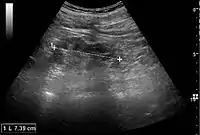

Kidney ultrasonography is useful for diagnostic and prognostic purposes in chronic kidney disease. Whether the underlying pathologic change is glomerular sclerosis, tubular atrophy, interstitial fibrosis, or inflammation, the result is often increased echogenicity of the cortex. The echogenicity of the kidney should be related to the echogenicity of either the liver or the spleen (Figure 22 and Figure 23). Moreover, decreased kidney size and cortical thinning are also often seen and especially when disease progresses (Figure 24 and Figure 25). However, kidney size correlates to height, and short persons tend to have small kidneys; thus, kidney size as the only parameter is not reliable.[54]

Chronic renal disease caused by glomerulonephritis with increased echogenicity and reduced cortical thickness. Measurement of kidney length on the US image is illustrated by '+' and a dashed line.[54]